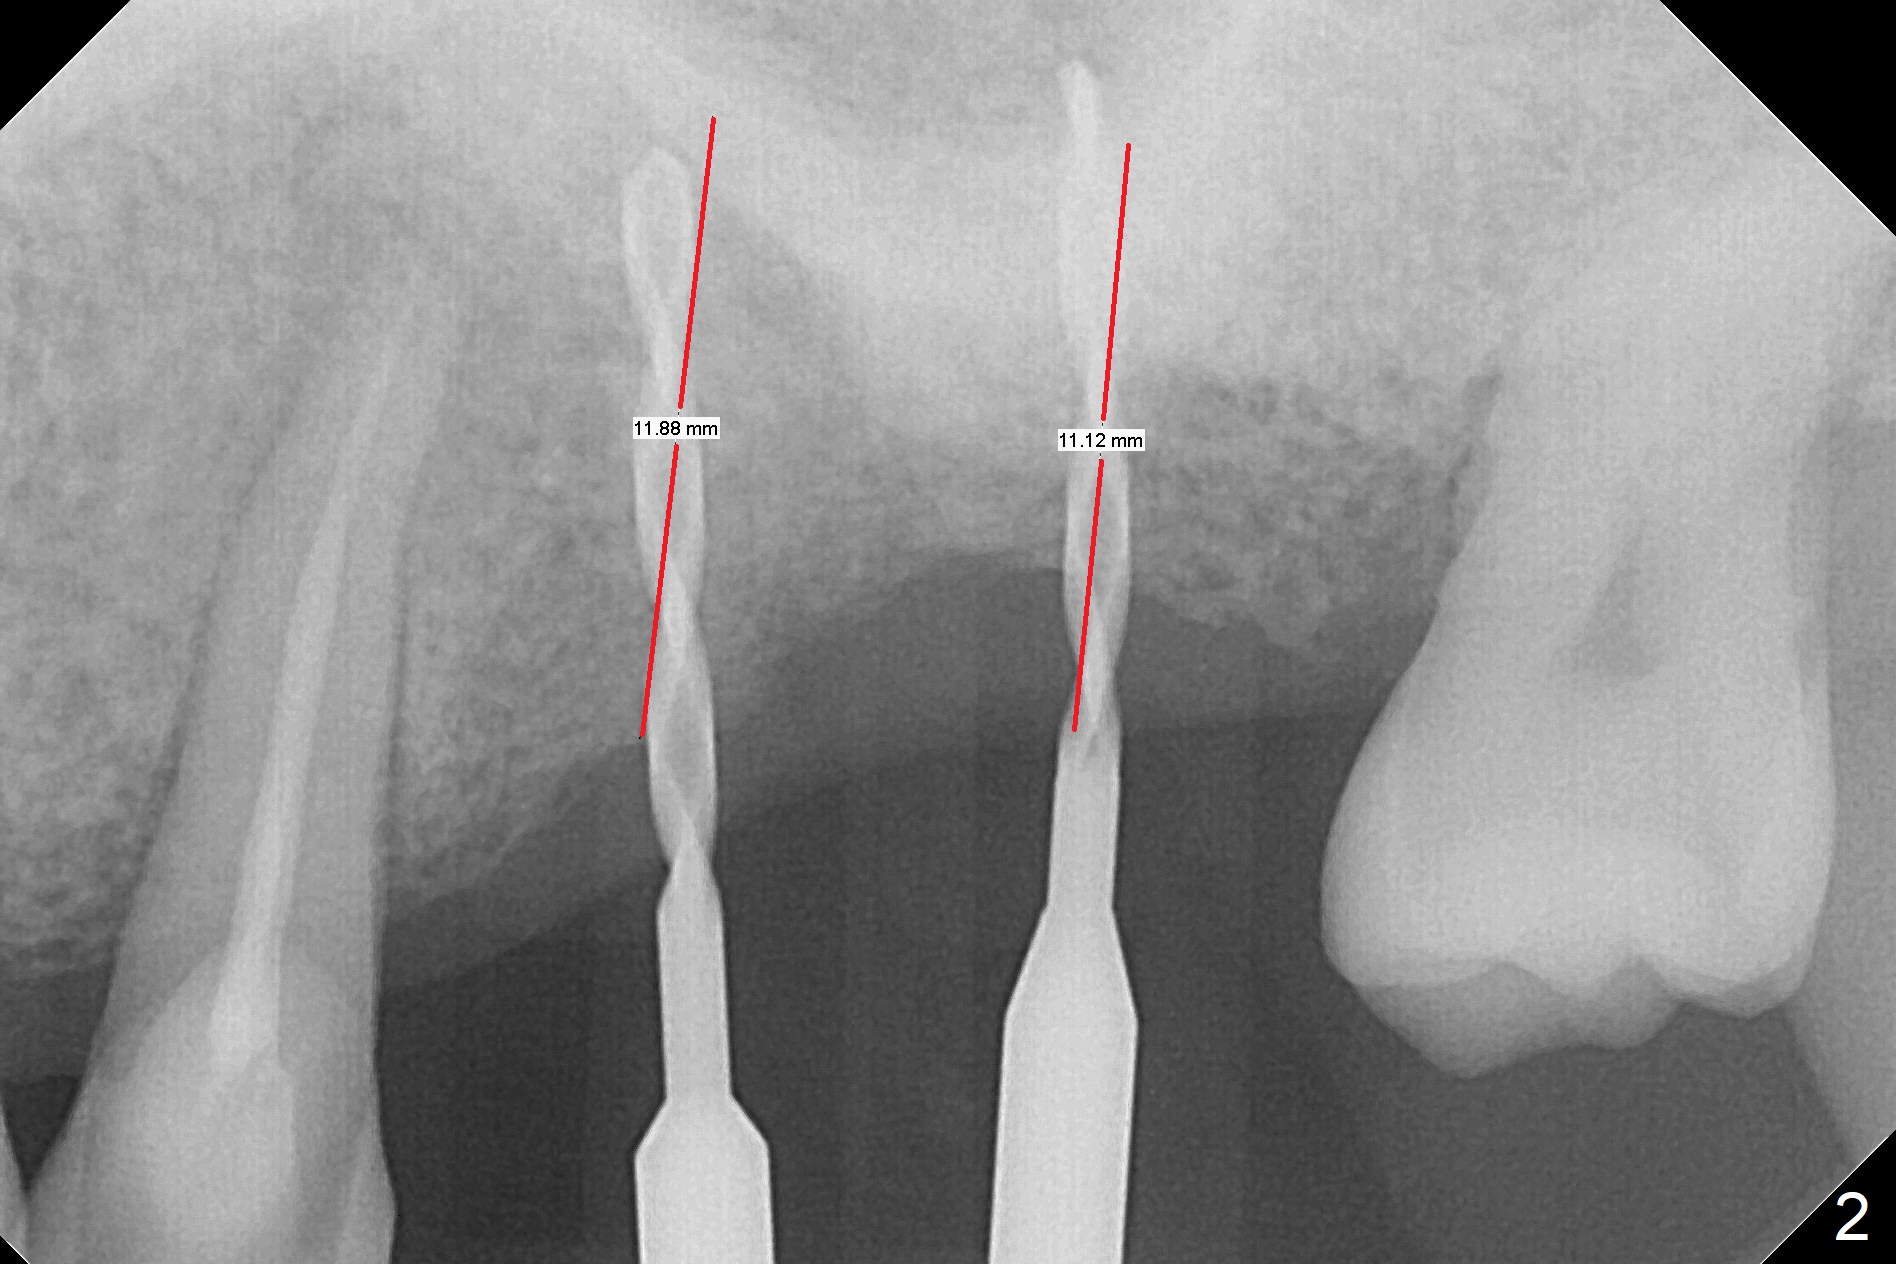

When 1.2 mm drill is used for osteotomy at #14 and 15, the bone feels to be soft (Fig.1). After change in trajectory (Fig.2), Expander 1 (Fig.3: E1, 1/1.6 mm) can be inserted at #14 and 15, while E2 (1.2/2.3 mm) cannot at full length at #14, suggesting hard bone. Osteotomy continues with drills until 4.1x14 mm, followed by insertion of E4 (2.4/3.7 mm) at #14, while osteotomy goes on until E3 (1.7/3.1 mm) at #15 (Fig.4). A 4.5x12 mm SM implant is placed with 50 Ncm (with insertion of a 5.8x4(2) mm abutment as a guide for #15 osteotomy, Fig.5). The apical portion of the osteotomy at #15 (Fig.5 red line) is finished with drills, leading to placement of a 4.5x12 mm implant (>50 Ncm) and 4.8x4(2) mm abutment (Fig.6). With bone density is more than 200 units, bone expansion appears to be not indicated. The patient returns for #13-15 crown prep 4.5 months postop (Fig.7). Abutments change to 5.8x5(3) and 5.8x4(3) mm at #14 and 15, respectively with mesial reduction of the tooth #16 (curved line) before impression. Minimal bone loss is observed 1 year 5 month post cementation (Fig.8,9), thanks to pre-existing wide bone.